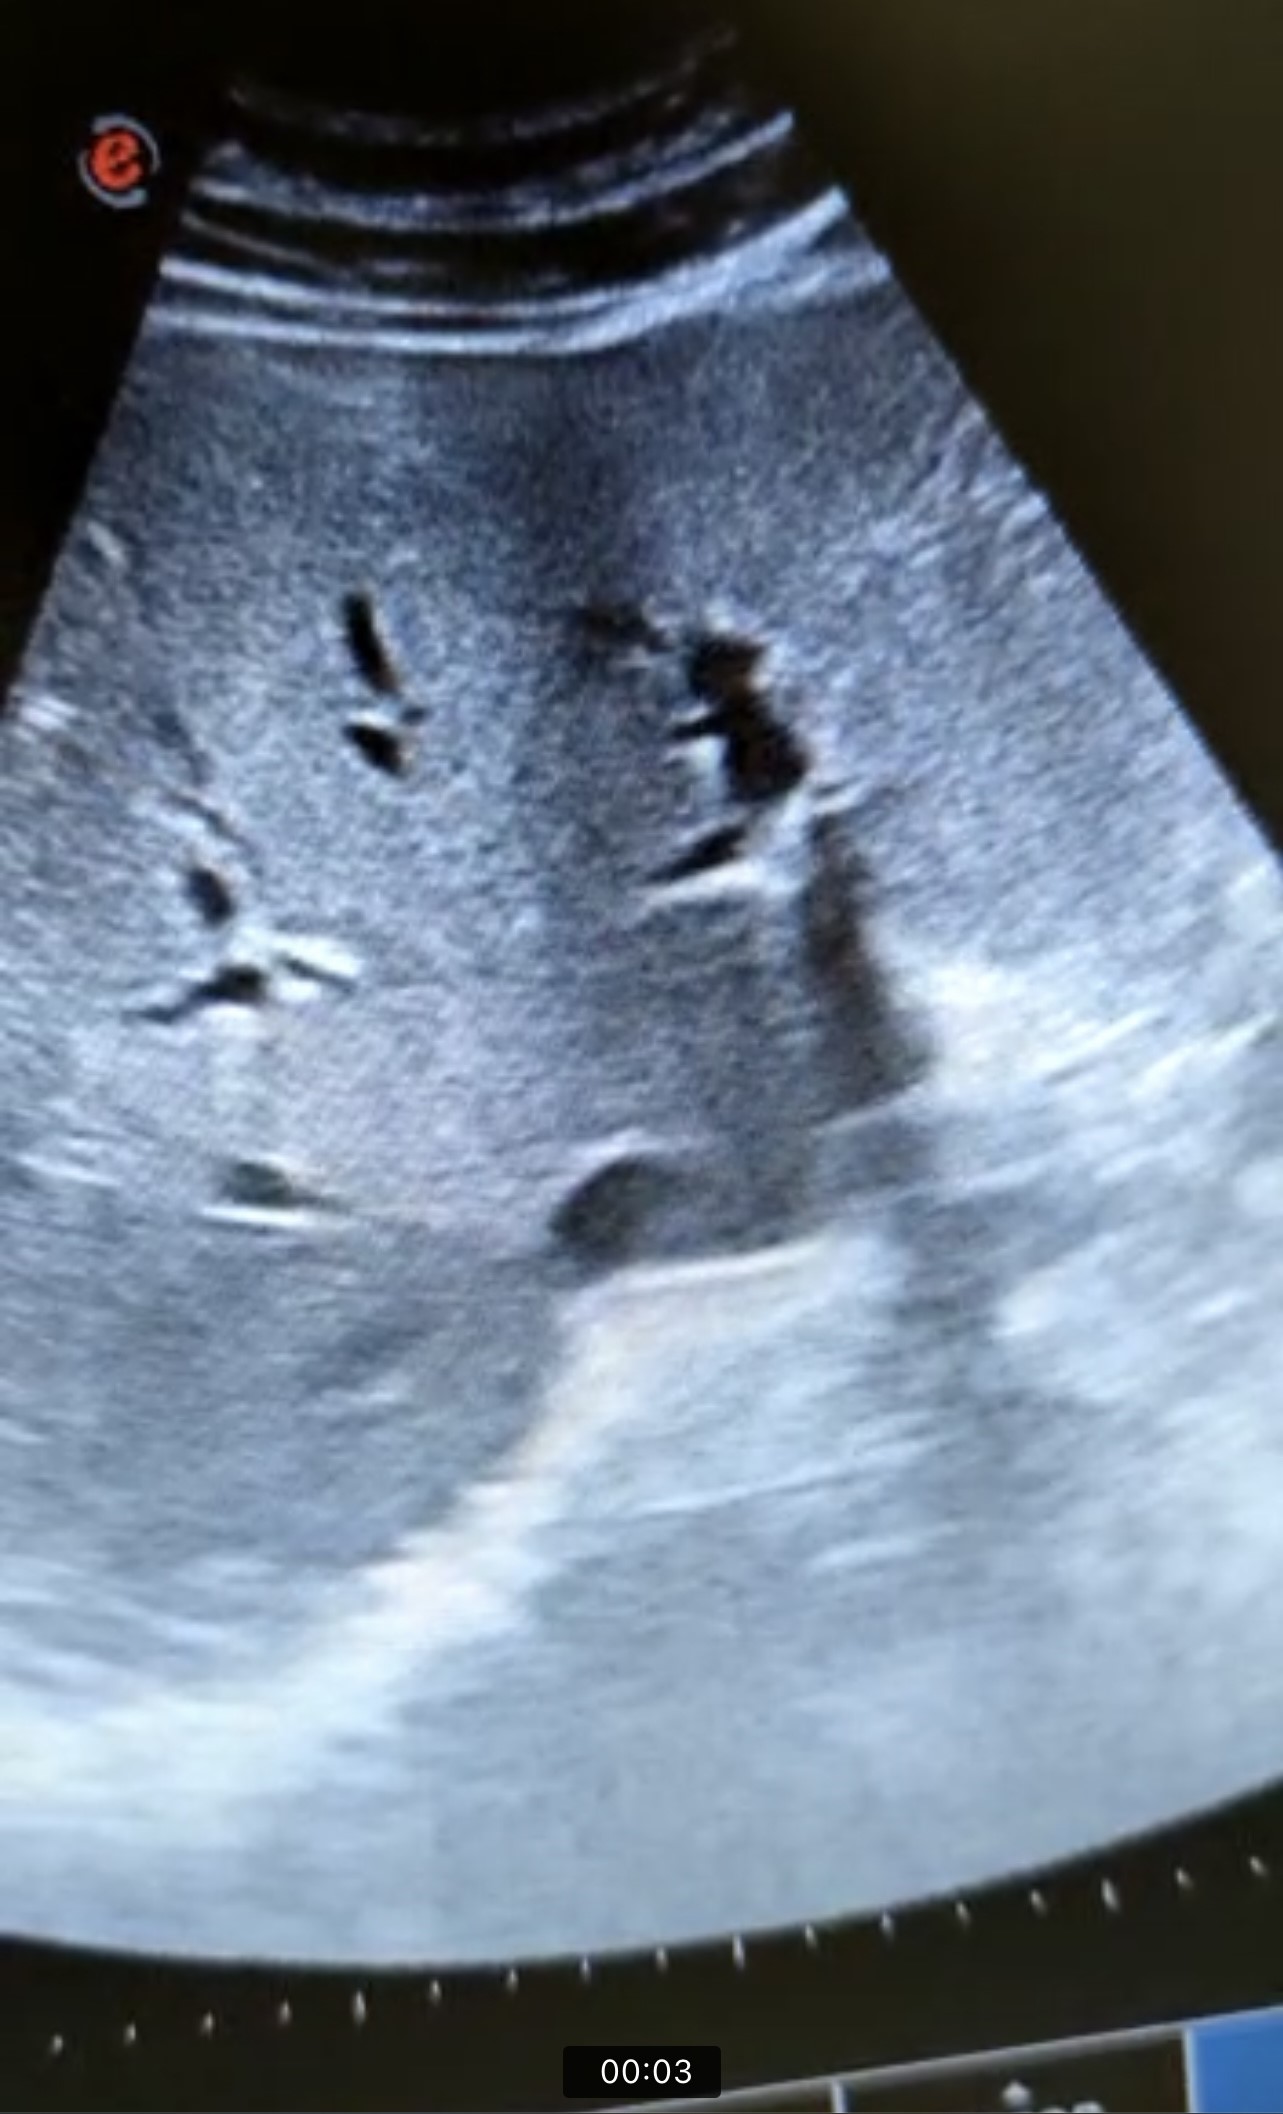

En la ecografía se observa ectasia de la vía biliar intrahepática conformando un patrón de doble carril.

No se visualizan colelitiasis.